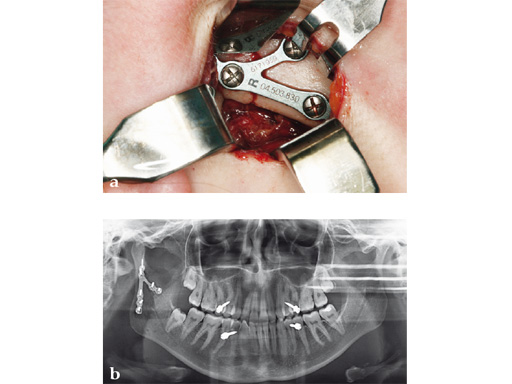

The lambda plate comes in a left and right version. It emulates a two-plate technique as its specific shape and 7-hole design with the width of a single plate at the top segment allows the surgeon to advance the lambda plate high up into the very narrow zone of the condylar neck just below the head. The fixation arms straddle the mandibular canal to avoid injury risk of the inferior alveolar nerve.

The lambda plate can be placed using retromandibular or submandibular surgical approaches. For positioning, the straight 5-hole segment is placed parallel to the posterior ramus border aligned with the condylar head. If required the anterior arm may be bent to fit the bony surface below the sigmoid notch.